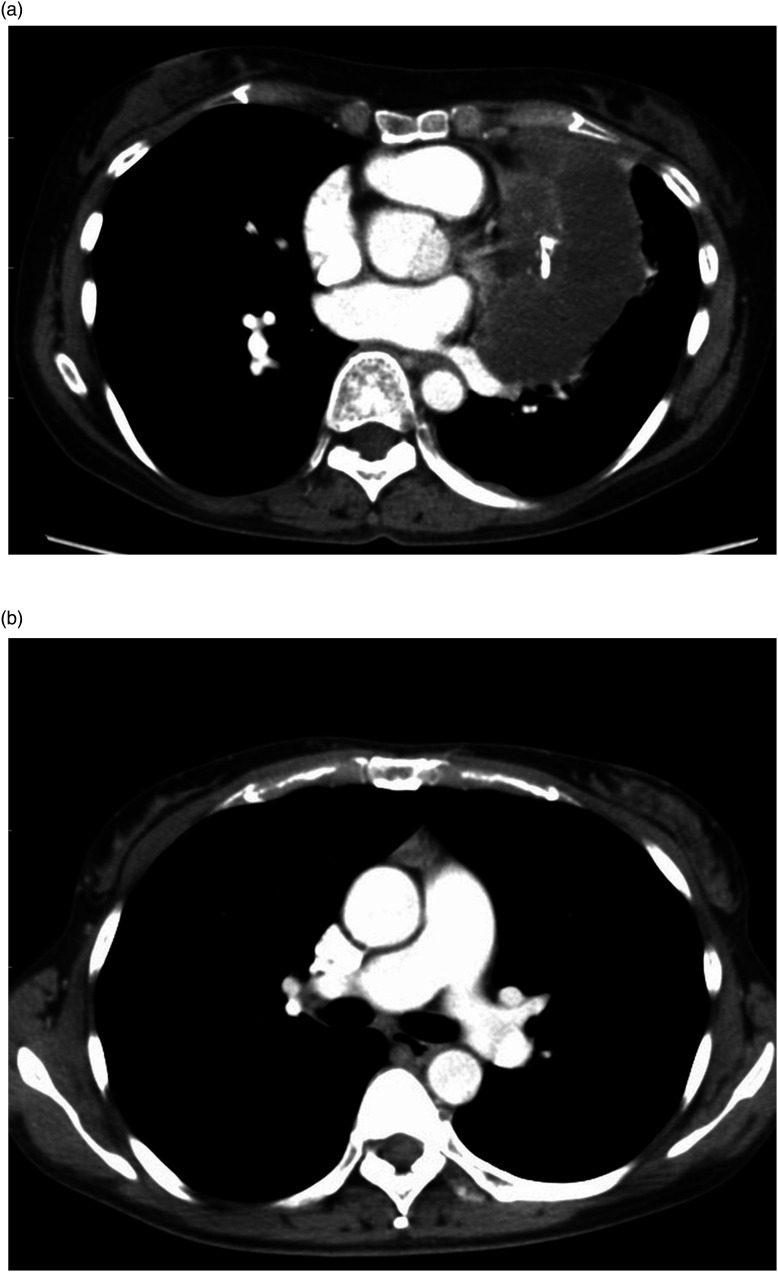

Purpose: To develop a CT-based DL model to distinguish between low-risk and high-risk thymoma and to compare the diagnostic performance of radiologists with and without the DL model.

Material and methods: 159 patients with 160 thymomas were included. A fine-tuning VGG16 network model with Adam optimizer was used, followed by k-fold cross validation. The dataset consisted of three axial slices, including the maximum tumor size from the CT volume data. The data were augmented 50 times by rotation, zoom, shear, and horizontal/vertical flip. Three independent networks for the CT dataset were considered, and the result was determined by voting. Three radiologists independently diagnosed thymomas with and without the model. The area under the curve (AUC) of the diagnostic performance was compared using receiver operating characteristic analysis.

Abstract Image